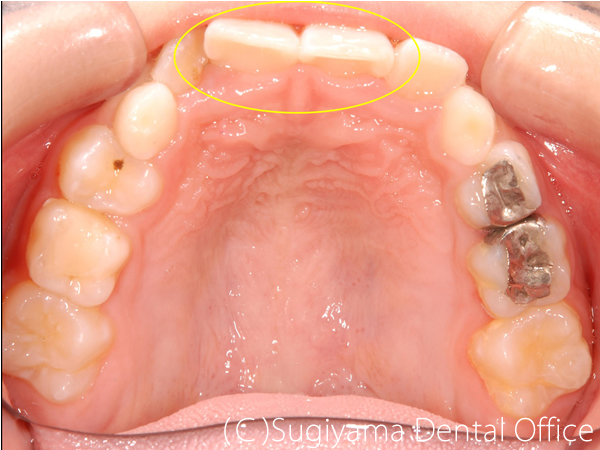

10歳の女性です。 術前写真を見ると、上の前歯2本が内側に傾斜していることがわかります(丸印)。 このような歯の傾斜によって下のあごの位置が奥に押し込まれ顎関節症になる方が少なくありません。